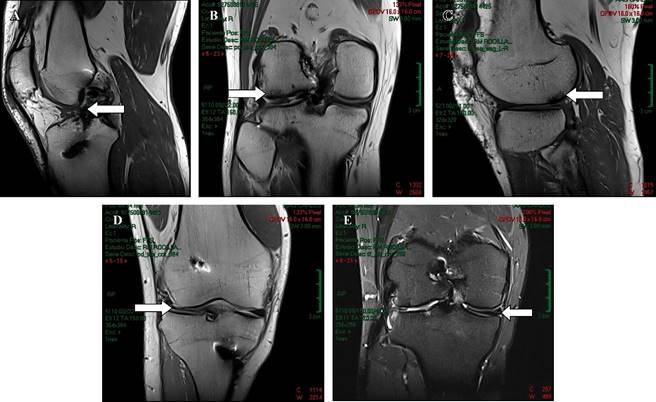

Se empieza abordaje diagnóstico con radiografías convencionales de rodilla derecha en proyecciones anteroposterior y lateral (Figura 1), así como resonancia magnética simple de rodilla para valorar de forma específica estructuras intraarticulares, características de lesiones condrales y del remanente meniscal en el compartimento lateral. Las imágenes de resonancia magnética arrojan los siguientes resultados: injerto de ligamento anterior adelgazado, de aspecto no competente, con disposición vertical e incipiente tejido fibrocicatricial ventral (Figura 2A); cambios en compartimento femorotibial lateral con adelgazamiento condral con zonas de delaminación, fisuras de espesor completo y edema subcondral (Figuras 2B-C); cambios por meniscectomía lateral (Figura 2D); menisco medial con un desgarro oblicuo que muestra apertura a la superficie articular condilar en un corte (Figura 2E).

Figura 2: A) Resonancia magnética simple de rodilla derecha en un corte sagital en secuencia T1 en la que se observa injerto de ligamento cruzado anterior adelgazado (flecha blanca) de aproximadamente 5.65 mm de grosor. B) Resonancia magnética simple de rodilla derecha en un corte coronal y C) sagital en secuencia T1, en las cuales se observan lesiones condrales con zonas de delaminación (flechas blancas) localizada al compartimento femorotibial lateral. D) Resonancia magnética simple de rodilla derecha en un corte coronal en secuencia T1 que muestra remanente posterior a meniscectomía lateral (flecha blanca). E) Resonancia magnética simple de rodilla derecha en un corte coronal en secuencia T2, se observa desgarro oblicuo en la unión del cuerpo con el cuerno posterior del menisco medial (flecha blanca).